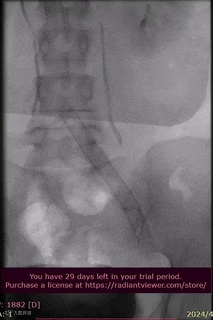

病例分享

山西省人民医院使用分享。

手术过程